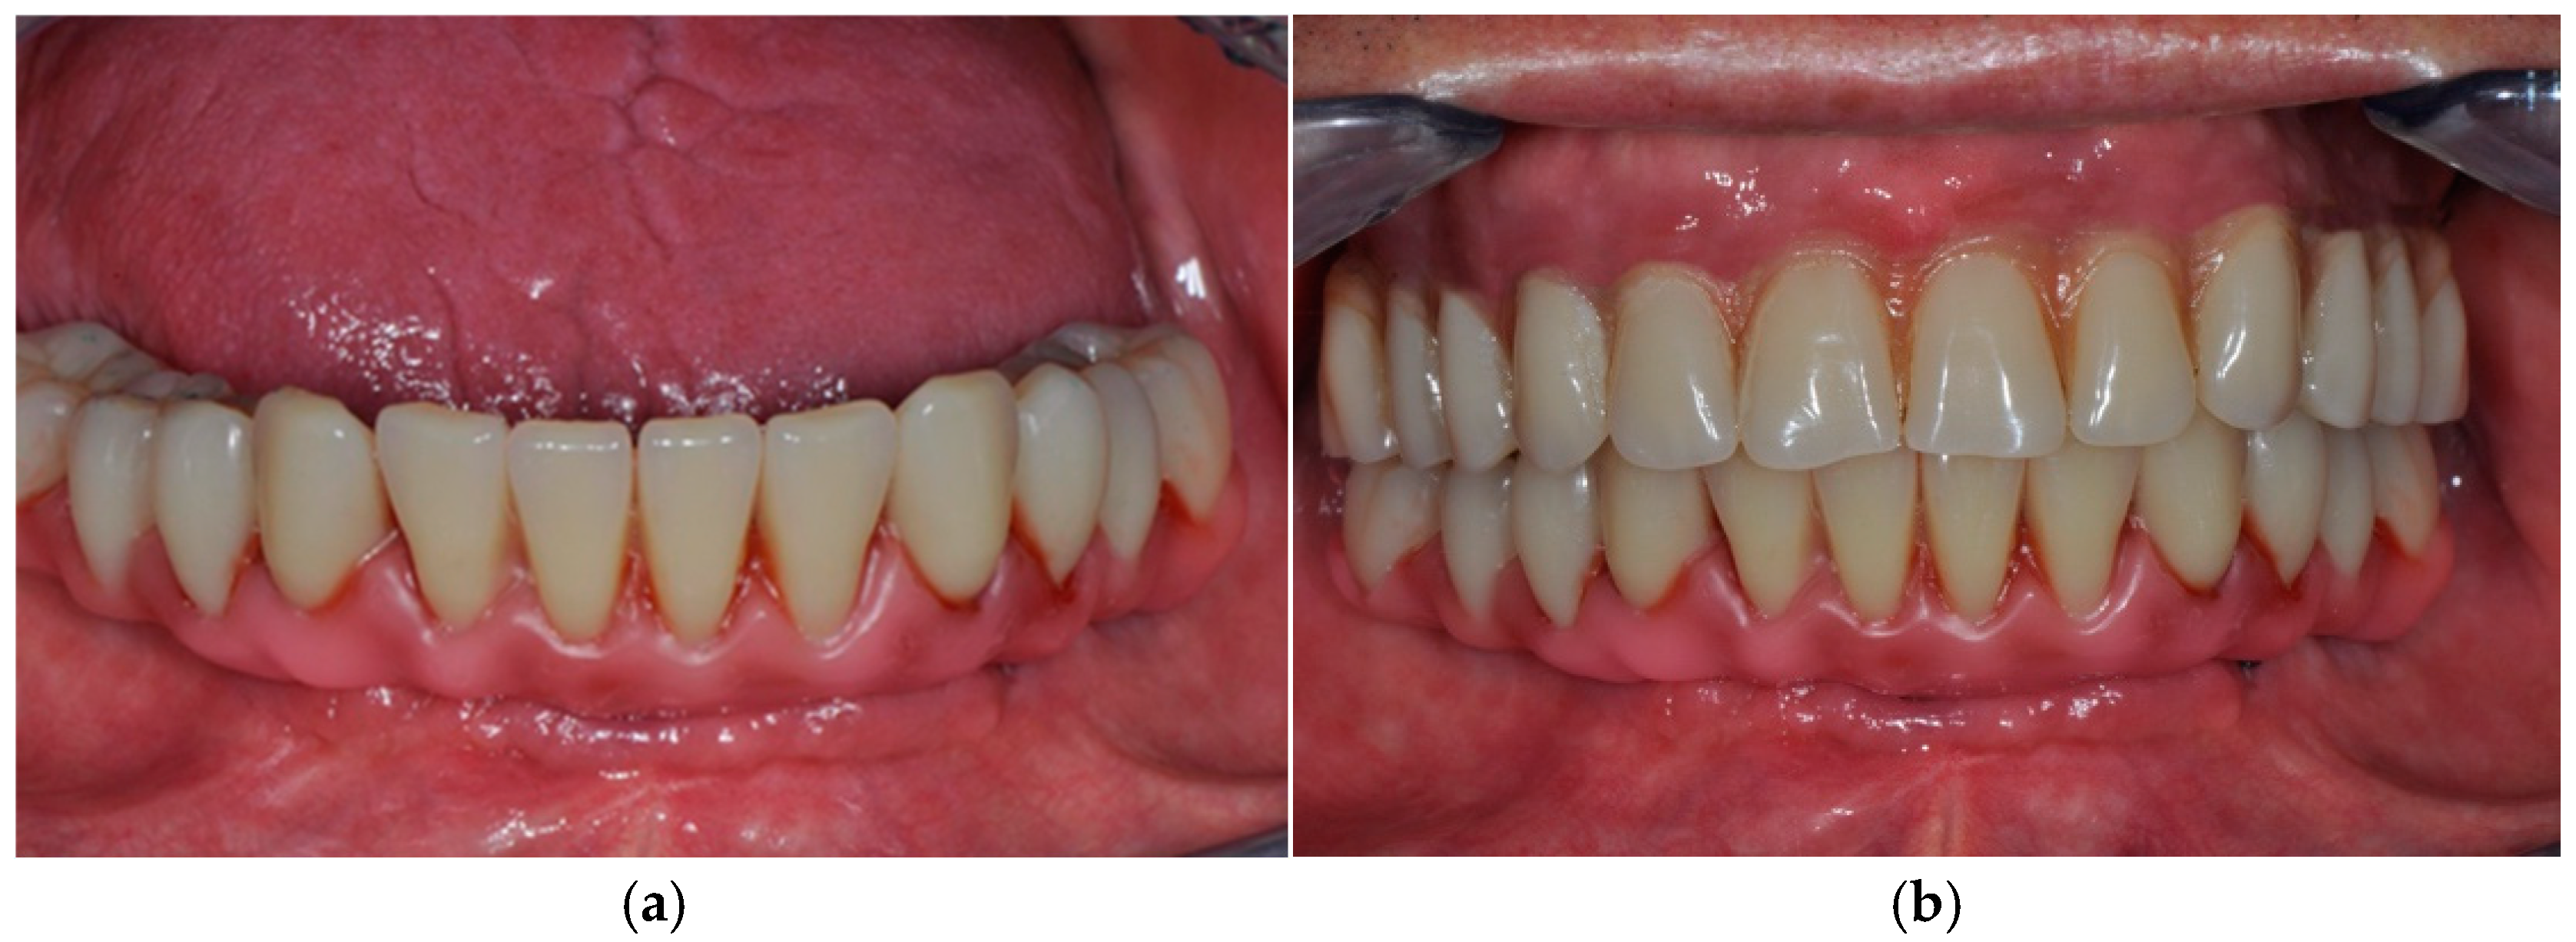

3. Case Presentation